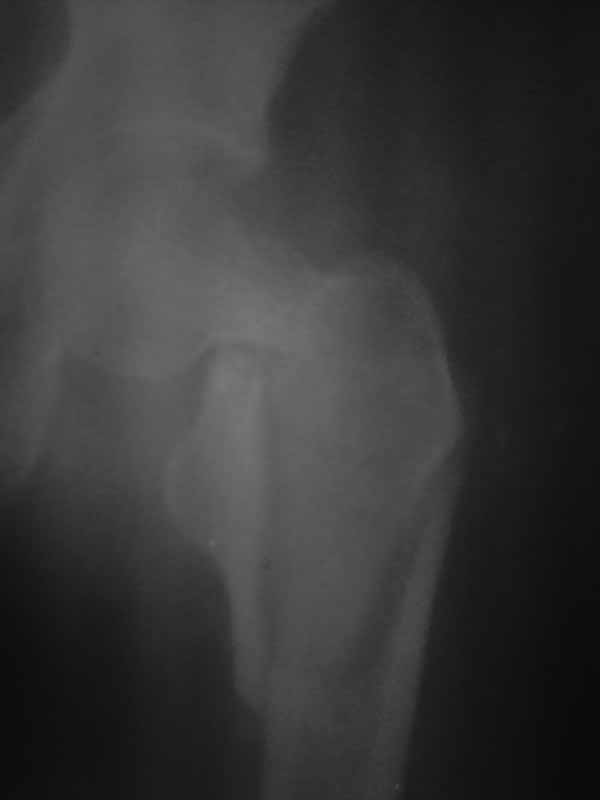

Re: перелом шейки бедра

Хотелось услышать дискуссию, по-этому выложил некачественный снимок с вопросом. Стараюсь выложить немного лучше. Гамму она приобрести не сможет. Смущает то что шейка больно хлипкая и винтом развалим ее до конца. На снимке кажется что и фрагмент шейки также сломан вдоль.